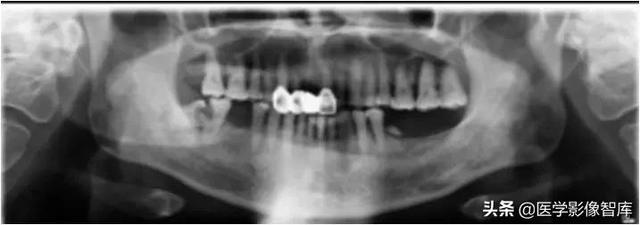

咀嚼肌间隙、颌下间隙、左侧颞下间隙,颊间隙,翼颌间隙

男,55岁,左下后牙反复肿疼1年余,加重1月余,疼痛剧烈伴张口受限,面部肿胀。

咀嚼肌间隙有脓肿形成。